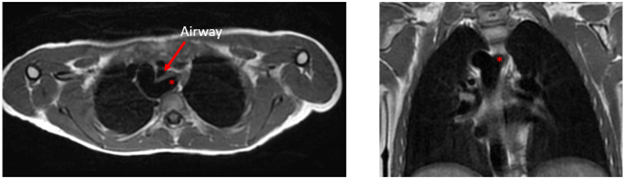

A diverticulum of Kommerell is an outpouching from the proximal descending aorta which gives rise to an aberrant subclavian artery and is also the site of ductal insertion. The diverticulum serves as a surrogate for the location of the ligamentum arteriosum (site at which the patent ductus arteriosus was present but then closed). Although the ligamentum will not fill with contrast on CMR, it forms one limb of the ring. Patients who are symptomatic due to tracheal or esophageal compression or who have a double aortic arch typically need surgical intervention. Black blood imaging can be instrumental in simultaneously visualizing the vasculature and the airway. In the figure below, the diverticulum of Kommerell is denoted with a red asterisk on axial (left) and coronal (right) images in a patient with a right aortic arch and aberrant left subclavian artery. A non-contrast MRA is also typically acquired as part of the CMR exam. When these non-contrast sequences are not diagnostic, a post-contrast MRA can provide a clear delineation of the vascular anatomy.